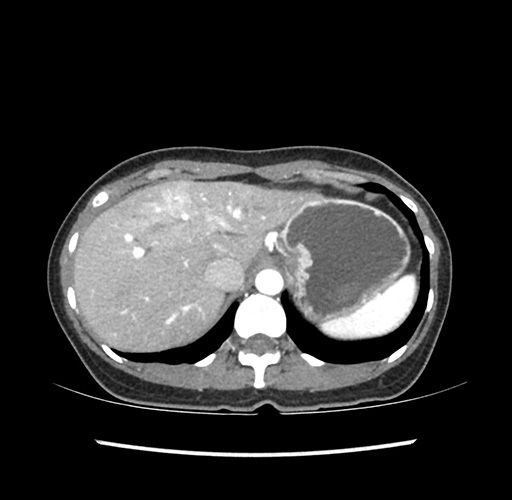

Imaging Analysis

Look through the patient's CT scan to identify any areas of concern for the necessary procedure.

Based on your CT findings, which issue(s) would give reason for "planned slowing down moment(s)" in this case?